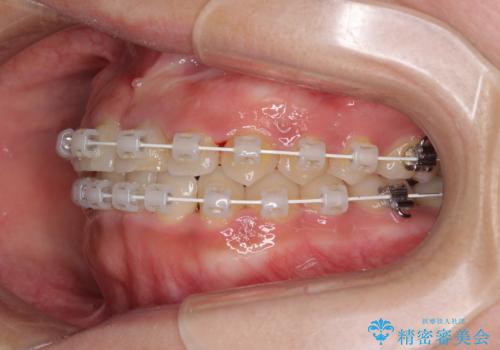

前歯のクロスバイトと変色した歯 ワイヤー矯正とセラミック治療

- 前歯のクロスバイトと神経を取り除いた後に変色してしまった前歯を気にして来院された患者様です。

ワイヤー矯正により矯正治療を行った後に、前歯の補綴治療を行うこととしました。

インビザラインでの矯正治療も十分に対応可能でしたが、自己管理の煩わしさから、ワイヤー矯正を行うこととしました。